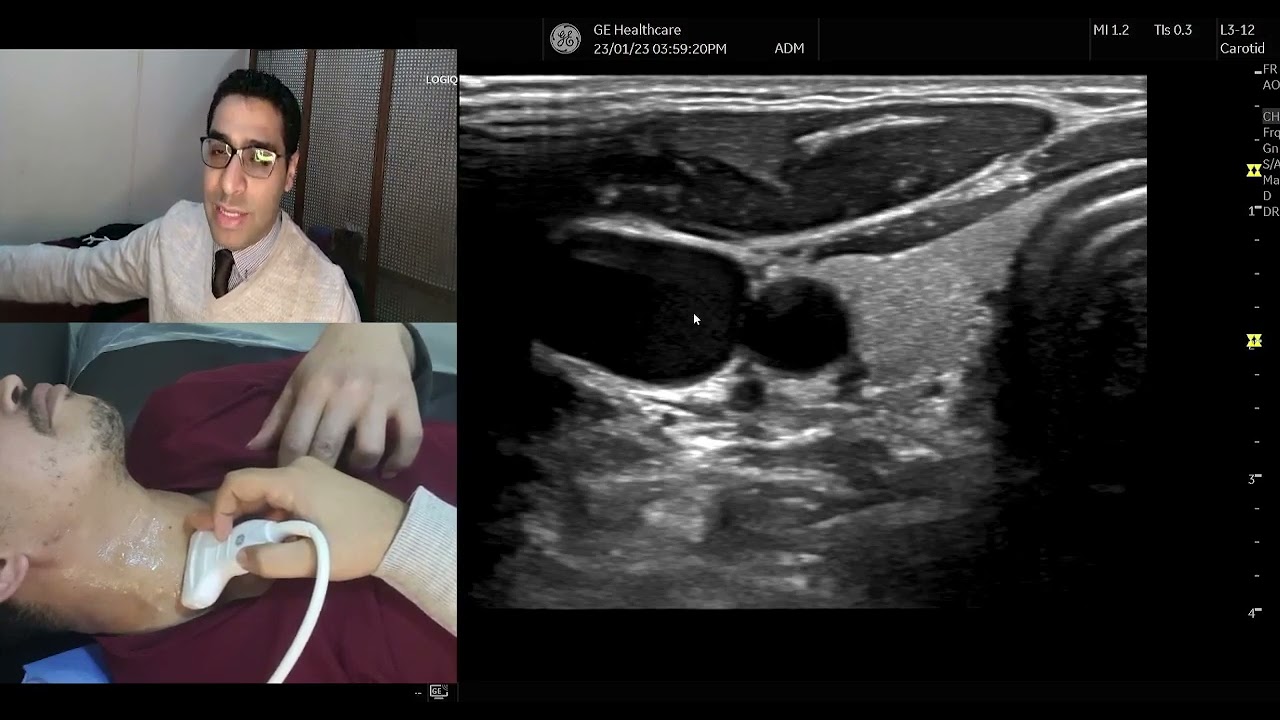

Demonstration of Carotid doppler technique  (Arabic)

Автор: Dr.Kareem A.Abdelaziz (SonoMaster)